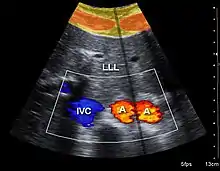

A normal appendix without and with compression. Absence of compressibility indicates appendicitis.[97] Compression is used in this ultrasonograph to get closer to the abdominal aorta, making the superior mesenteric vein and the inferior vena cava look rather flat.

Compression is used in this ultrasonograph to get closer to the abdominal aorta, making the superior mesenteric vein and the inferior vena cava look rather flat.